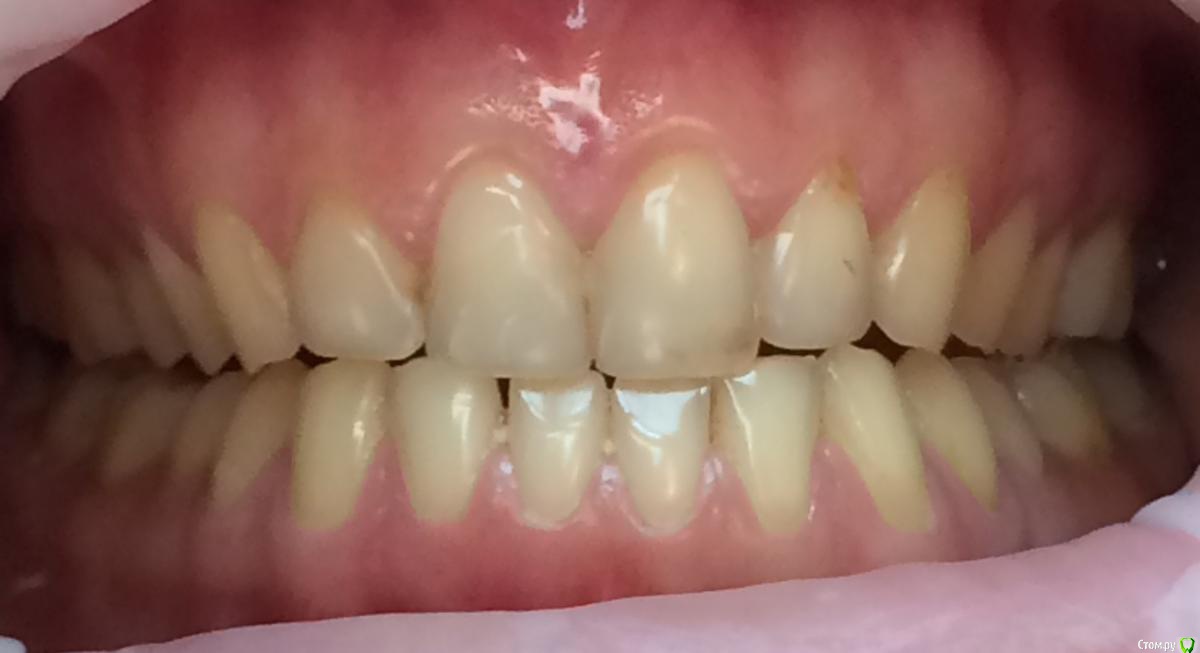

Larnary Опубликовано 28 июля, 2015 Поделиться Опубликовано 28 июля, 2015 (изменено) Добрый день!Ко мне обратилась пациент 1988 гр с жалобой на стираемость зубов и постоянные сколы пломб.Объективно небная поверхность верхних резцов стерта до дентина. Окклюзионная стираемость жевательной группы зубов.Прошу помочь с выявлением причины такой стираемости зубов и оптимальноно метода лечения Изменено 28 июля, 2015 пользователем Larnary Ссылка на комментарий

Bobby Опубликовано 29 июля, 2015 Поделиться Опубликовано 29 июля, 2015 Фасетки стираемости на нёбных поверхностях верхних резцов и вестибулярных поверхностях нижних резцов обусловлены малым оверджетом - недостаточная щель по саггитали, поэтому и будут колоться реставрации, а ткани зубов истираться. Фрадеани про это на своём курсе рассказывал и показывал видео как это диагносцировать и что с этим делать. Что вообще хочет пациентка и на что готова? Эти вопросы лучше сразу решать на первичной консультации, а то делаете диагностики, всё рассчитываете, распинаетесь, а они потом: "ой, я пока не готов/а к такому плану лечения" и всё заканчивается композитной мазнёй в другой клинике. 5 Ссылка на комментарий

zzkz Опубликовано 29 июля, 2015 Поделиться Опубликовано 29 июля, 2015 Со слов Коиса понял, что в данном случае было бы достаточно создать достаточное функциональное пространство для резцов нижней челюсти, путем брекетов например, вывести передние резцы в/ч в протрузию Ссылка на комментарий

Bobby Опубликовано 29 июля, 2015 Поделиться Опубликовано 29 июля, 2015 Со слов Коиса понял, что в данном случае было бы достаточно создать достаточное функциональное пространство для резцов нижней челюсти, путем брекетов например, вывести передние резцы в/ч в протрузиюИменно! А иногда это пространство можно создать за счёт легкого изменения угла коронковой части зубов (за счёт керамических рестарваций - если к ним есть показания, а в данном случае они как раз есть). Ссылка на комментарий

Skip Опубликовано 3 августа, 2015 Поделиться Опубликовано 3 августа, 2015 Со слов Коиса понял, что в данном случае было бы достаточно создать достаточное функциональное пространство для резцов нижней челюсти, путем брекетов например, вывести передние резцы в/ч в протрузию Не самое лучшее решение при глубоком прикусе. Довольно часто приходится видеть, как попытки решения проблем глубокого прикуса терпят неудачу из-за непонимания принципов передней направляющей. Первое, с чем Вы здесь сразу можете столкнуться, когда будете "выводить резцы в/ч в протрузию", показано на рисунке ниже: http://i11.pixs.ru/storage/4/5/6/09765ukeng_6235790_18261456.jpg Верхние резцы будут наталкиваться на нижнюю губу, из-за чего могут возникнуть проблемы с фонетикой, да и эстетически ничего хорошего. Мало того, полученный результат будет крайне нестабилен вследствие нарушенного нейромышечного равновесия нейтральной зоны, об этом можно почитать у Доусона. Поэтому грамотные ортодонты, зная об этом, проводят не вестибулярный наклон, а интрузию верхних и нижних резцов. Да и говоря в общем, проблема стираемости, при глубоком прикусе, обусловлена не "малым оверджетом", как выразился Александр. Основная проблема состоит в том, что при отсутствии устойчивых удерживающих контактов нижних резцов с верхними в ЦС, происходит их зубоальвеолярная экструзия. Глубокие прикусы, если там решена проблема этих удерживающих контактов на нёбной поверхности коронок верхних резцов , будет среди самых устойчивых видов окклюзии, т.к. с disclusion в боковых отделах здесь почти не бывает проблем. С интерференциями в задних отделах нужно тоже разобраться и делать это нужно в ЦС, перенеся модели в артикулятор с лицевой дугой. На видео можно проследить, к эти интерференции могут стать причиной стираемости передних резцов. http://www.youtube.com/watch?v=2wRffJl82dc http://www.youtube.com/watch?v=My3K-B78iLg 1 Ссылка на комментарий

Maverick Опубликовано 9 августа, 2015 Поделиться Опубликовано 9 августа, 2015 (изменено) Думаю в данном кейсе интрузия резцов будет нежелательна, десневые контуры фронтальной группы зубов выглядят хорошо, ровно, нет разницы в высоте(если конечно не были внесены изменения в контур десны, типа пластик) . И тут не дентальный глубокий прикус, а скелетный, как было отмечено выше. Еще один негативный момент в интрузии, который играет важную роль , так это искусственное состаривание пациента, верхняя губа имеет свойство опускаться со временем, что только ухудшит картину эстетики улыбки. Экспозиция резцов очень важный критерий в планировании лечения, тут надо отталкиваться от возраста пациента. Думаю у данного пациента, учитывая возраст, позицию фронтальных зубов , уровень десны идеально будет завысить прикус в боковом отделе и вывести в небольшой вестибулярный наклон фронт на брекетах, либо как упоминалось выше за счет изменение наклона коронковой части, путем керамических реставраций, что удобнее для пациента в плане финансовых и временных затрат. P.S. Такое ощущение , что есть определенные проблемы с клыковым ведением, поэтому и интерфреннции возникают в боковом отделе. Поэтому хорошо было бы увидеть все в артикуляторе, чтобы уже точно знать причину Угол межрезцовый идеальный 132 градуса плюс минус 10 град. Изменено 9 августа, 2015 пользователем Maverick 2 Ссылка на комментарий